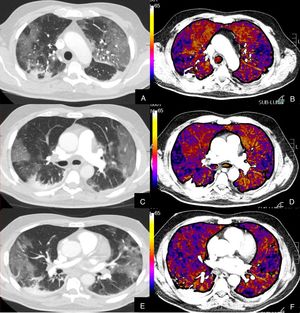

Paciente con alta sospecha de COVID-19, con D-dímero de 80.000, disnea y fiebre de 15 días de evolución.

Imágenes axiales de la angiografía pulmonar con TC y mapa de yodo en ventana de pulmón (A, C, E) desde cayado hasta lóbulos inferiores y la correlación con el mapa de yodo (B, D, F) e imágenes axiales (G y H) en ventana de mediastino.

Parénquima con extensa afectación en «crazy paving» subpleural y peribroncovascular de predominio en segmentos posteriores, con TEP agudo en arteria lobar inferior derecha y segmentarias inferiores derechas (flechas blancas) y leve hipoperfusión periférica en LID (áreas parcheadas azules) en relación con el tromboembolismo.